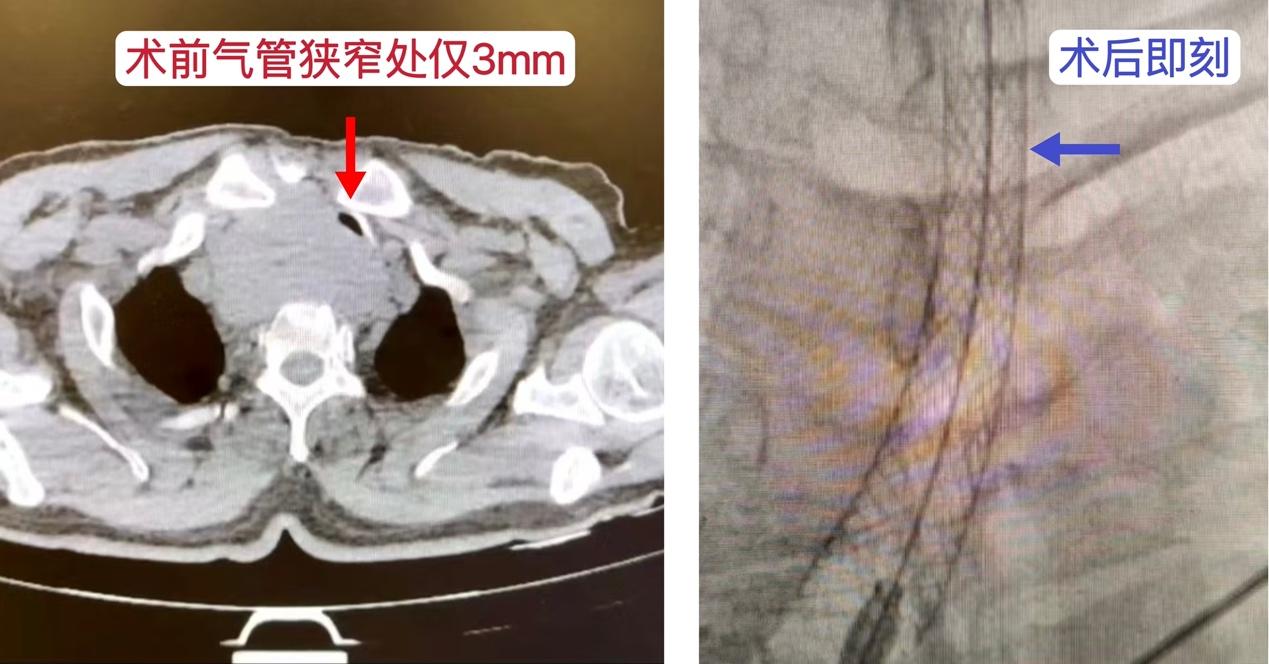

近日,吉大三院甲状腺疾病多学科团队成功救治了一例危重甲状腺疾病患者,为患者及家属带来了生命的希望。该患者甲状腺癌术后14年,近半年出现严重呼吸困难,CT检查发现肿瘤复发位于胸骨后,并达气管隆突水平,压迫气管导致其最狭窄处仅有3毫米,病情危急。患者曾多次辗转全国多家医院求医未果,最终求治于我院甲状腺外科孙辉教授。

经过多学科团队的细致讨论,最终确定了“解决呼吸困难为先,根治为后”的分期治疗方案。首先针对呼吸困难症状及窒息风险,进行气管支架置入术,后续再针对肿瘤复发问题开展治疗。19日下午,孙昱教授团队在陈鹏教授团队的密切配合下顺利完成气管支架置入术,术后患者的呼吸困难症状显著缓解,状态逐渐平稳。该手术既有效解决了患者最为急迫的症状,也为后续治疗争取了宝贵的时间,奠定了坚实的治疗基础。